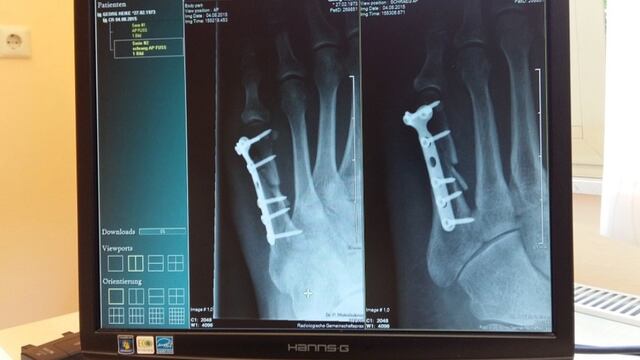

En el estudio se analizaron a 55 mil participantes de todo Reino Unido, en los que se observaron 3 mil 941 casos de fracturas totales, siendo la principal diferencia entre los veganos y los consumidores de carne la probabilidad de sufrir una rotura de cadera, que en los primeros era 2,3 veces más alta.